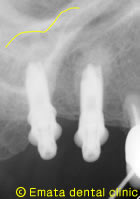

術中のレントゲンです。

奥歯の上には上顎洞という空洞(黄色の線)がありこのままではインプラントが上顎洞内に突き抜けてしまうためインプラントの手術ができません。